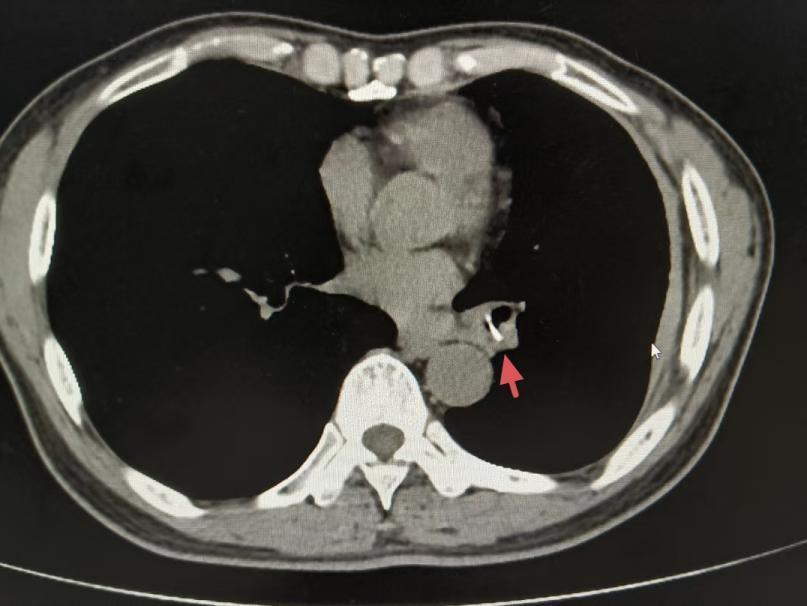

在市十二病院再次接受的胸部CT后果暴露,陈叔左下肺支气管有可疑异物影像。追问病史时,陈叔回忆起一年前吃鱼时曾有剧烈呛咳史,但其时症状自行缓解,该院呼吸科副主任医师陈子谓机敏地捕捉到了这一关节信息,随后的纤维支气管镜查验也印证了他的猜念念。镜下明晰可见一块疑似骨头的异物嵌顿于左下肺支气管,周围组织已形成化脓性炎症。困扰陈叔一年多的罪魁罪魁终于现形。

左下肺支气管可疑异物影像

左下肺支气管可疑异物影像